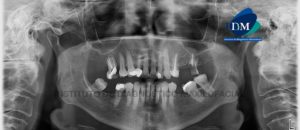

164 – Reabsorcion radicular severa

Paciente masculino de 17 años acude al Instituto de Diagnóstico Maxilofacial para evaluación de la pieza 2.1. A la evaluación de la radiografía panorámica se